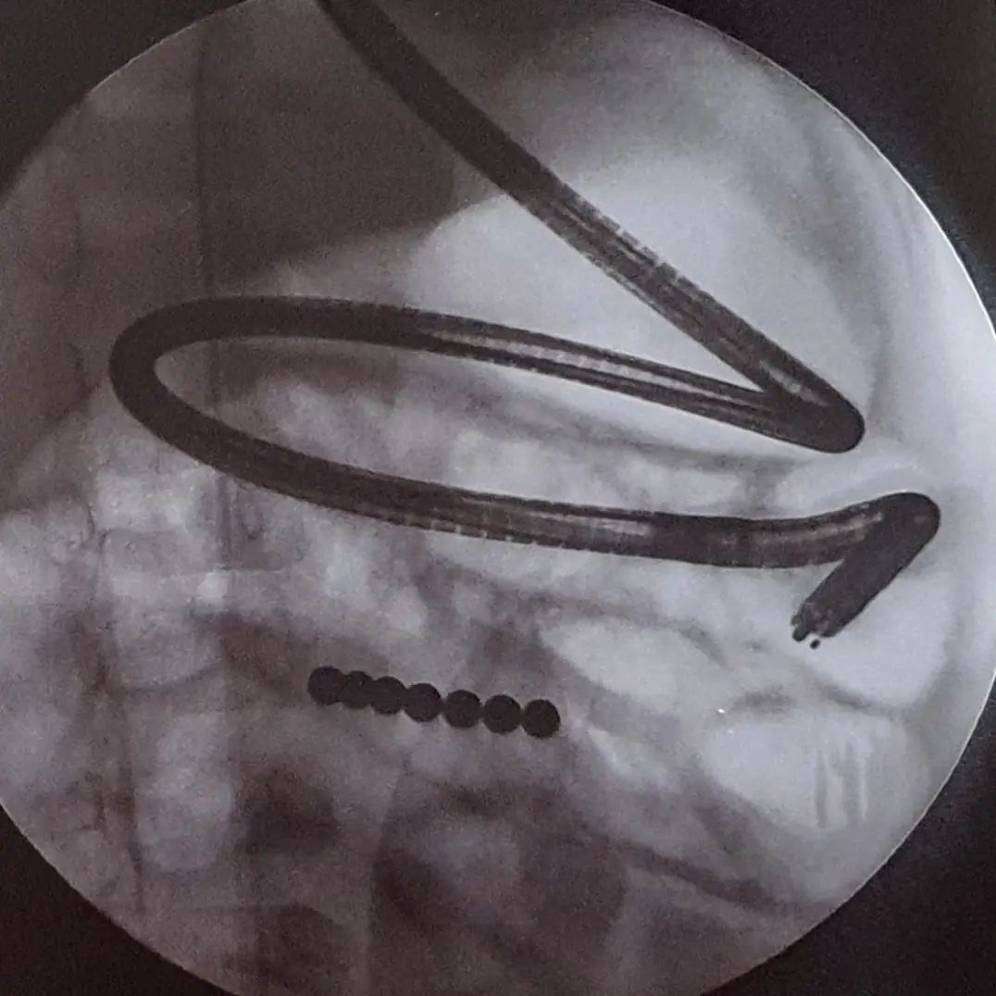

Untuk itu ayah bunda, selalu awasi anak balita saat bermain terutama dengan benda-benda kecil seperti magnet. Dokter Ariani Dewi Widodo, seorang spesialis anak, membagikan kasus anak yang menelan magnet bukan hanya satu tapi tujuh.

" Bulan Juli, Bunda menemukan si adik yang sebentar lagi 2 tahun sedang mengulum bola magnet itu. Fiuhh... untung sempat terlihat sebelum tertelan. Selanjutnya semua sudah melupakannya, hingga Oktober 2021 anak mulai mual muntah, kembung, dan nyeri perut berulang. Begitu difoto, tampak rangkaian 7 butir bola magnet yang saling berhimpitan. Rupanya yang ditemukan sebelumnya hanya sebagian saja, sudah ada yang terlanjur tertelan," tulis dr. Ariani.

" Bila dua magnet atau lebih berada di usus pada saat yang bersamaan, atau magnet bersama benda metal lain, magnet akan saling menarik dan menjepit jaringan usus di tengahnya, sehingga tidak mendapat aliran darah dan mati. Akibatnya magnet bisa terbenam ke jaringan, tersangkut, dan tidak jarang menyebabkan usus bocor yang tentu fatal akibatnya," ungkap dr. Ariani.

Pada kasus yang ditangani dokter Ariani, anak tersebut awalnya bakal diberikan prosedur endeskopi untuk mengambil magnet, tetap letaknya terlalu jauh. Tak berhasil, akhirnya tim dokter memutuskan untuk melakukan operasi.

" Endoskopi dilakukan utk menariknya keluar, namun letaknya sangat jauh ke dalam. Jadi, dilanjutkan operasi oleh Dokter Bedah Anak handal Dr @cathlinefreya SpBA. Bola magnet tersangkut & menjepit jaringan usus. Ketujuh bola magnet berhasil dikeluarkan dengan sukses! Foto & post seizin orangtua & Humas @rsabhk demi kepentingan edukasi. Bersama kita saling mengingatkan dan menjaga," pesannya.